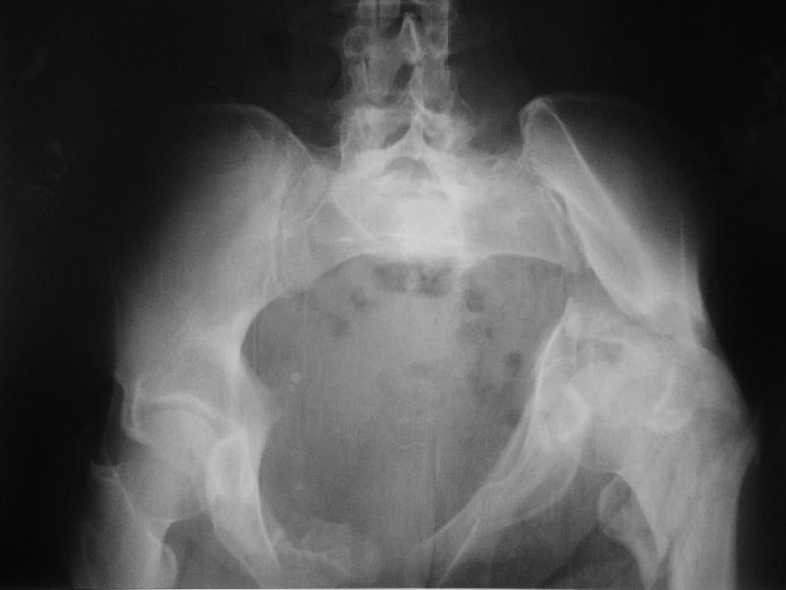

Больная 43 года (промышленный альпинист), 28.07.08 в результате падения с 5 этажа получила политравму: Перелом свода и основания черепа. Вертикально-нестабильное повреждение таза, осложнённое разрывом мочевого пузыря. Чрезвертельный перелом левого бедра. Перелом правой таранной кости, переломовывих правой кубовидной кости. Тупая травма живота, разрыв печени, ушиб почек. Забрюшинная гематома. В день травмы - лапаротомия, ушивание ран печени. Разрыв мочевого пузыря не диагностирован. Течение болезни осложнилось развитием мочевого затёка и обширной пред- и забрюшинной флегмоны, сформировался свищ мочевого пузыря. 19.8.2008 вскрытие, дренировние флегмоны, ревизия мочевого пузыря, обтурация мочевого свища (свищ закрылся в октябре), 1.10.2008 некрэктомия, пластика по Шеде-Лидскому правой кубовидной кости. По результатам КТ диагностирован рак правой почки (диагностическая находка), 8.10.2008 нефрэктомия справа. Переломы велись консервативно. Имеется вертикальное смещение левой половины таза с выраженным отведением крыла (клинически подвижности нет), несросшийся низкий двухколонный перелом левой вертлужной впадины с потерей конгруэнтности, укорочение около5 см, застарелый разрыв лонного сочленения, неправильно сросшиеся переломы обеих ветвей правой лонной кости с укорочением, патологическая подвижность лоно-седалищного фрагмента слева. Правая нижняя конечность неопорна, несмотря на то, что лежа прямую ногу поднимает, ходит на левой ноге (ортопедическая обувь) с костылями, справа тазобедренный ортез. Седалищные нервы работают.Урологи отпустили больную на 6 мес.

Мучаемся мыслями - как все это заставить ходить.Возможно ли первичное протезирование если просто синтезировать лонное сочленение с цементом и ванкомицином? Если делать большую реконструкцию, то с чего начать? Изрубить крыло и заполнить дефекты? Перерубить боковую массу и попытаться развернуть крыло обратно? Ждать год после закрытия свищей?